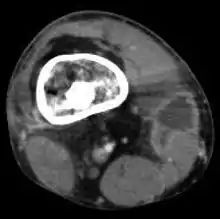

![]() | |

Osteomyelitis of the 1st toe | |